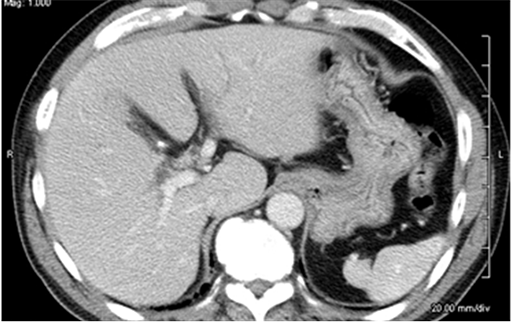

X線で得られた情報をもとに体を輪切り状に画像化し、内臓の状態を詳しく知る事が出来る検査です。造影剤を注射することで臓器周辺の血管が白く映し出されるため、さらに詳細な情報を得る事が出来ます。最近のCTは0.5mm程度の間隔で輪切りにして撮影することが出来るようになったばかりか、画像をコンピューター処理することで、色々な方向で撮影した写真や立体的な画像を作ることができます。図2Aは通常のCTで得られるお腹の臓器の輪切り像ですが、図2Bのような縦切りの写真を作成すると、胆管が全長にわたって見えるようになるため、輪切りでは分かりにくかったがんの位置が分かるようになります。このように胆管がんに対して最新のCTで検査をすれば、胆管全体を詳しく観察することができますので、がんの存在部位を正しく診断することができます。さらに、胆管周囲の血管とがんの位置関係を詳細に観察することができますので、どんな治療が一番効果的なのか判定することができます。